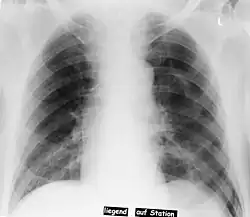

Röntgenbild des Thorax im Liegen: Pneumothorax nach Anlage eines zentralen Venenkatheters

Ein linksseitiger Spannungspneumothorax vor (oben) und nach (unten) Anlage einer Thoraxdrainage. Gut zu sehen ist die Verlagerung des Mediastinums hin zur gesunden Seite.

Besonders schwerwiegend ist ein Spannungspneumothorax, bei dem durch Verletzung der Lunge oder Brustwand ein Lippenventil entsteht, das mit jedem Atemzug weitere Luft in den Pleuraspalt zieht, ohne diese bei der Ausatmung entweichen zu lassen. Dadurch steigt der Druck in der betroffenen Brusthöhle an, komprimiert den Lungenflügel, schränkt damit die Atmung weiter ein, verschiebt das Mittelfell zur Gegenseite und behindert durch Verziehung und Kompression der Hohlvene den Blutrückfluss zum Herzen, sodass ein kritischer Blutdruckabfall bis hin zum Herz-Kreislauf-Stillstand resultieren kann. Man findet

• Im Röntgenbild ist von einem Spannungspneumothorax auszugehen, wenn das Mediastinum zur gesunden Seite hin verschoben ist.